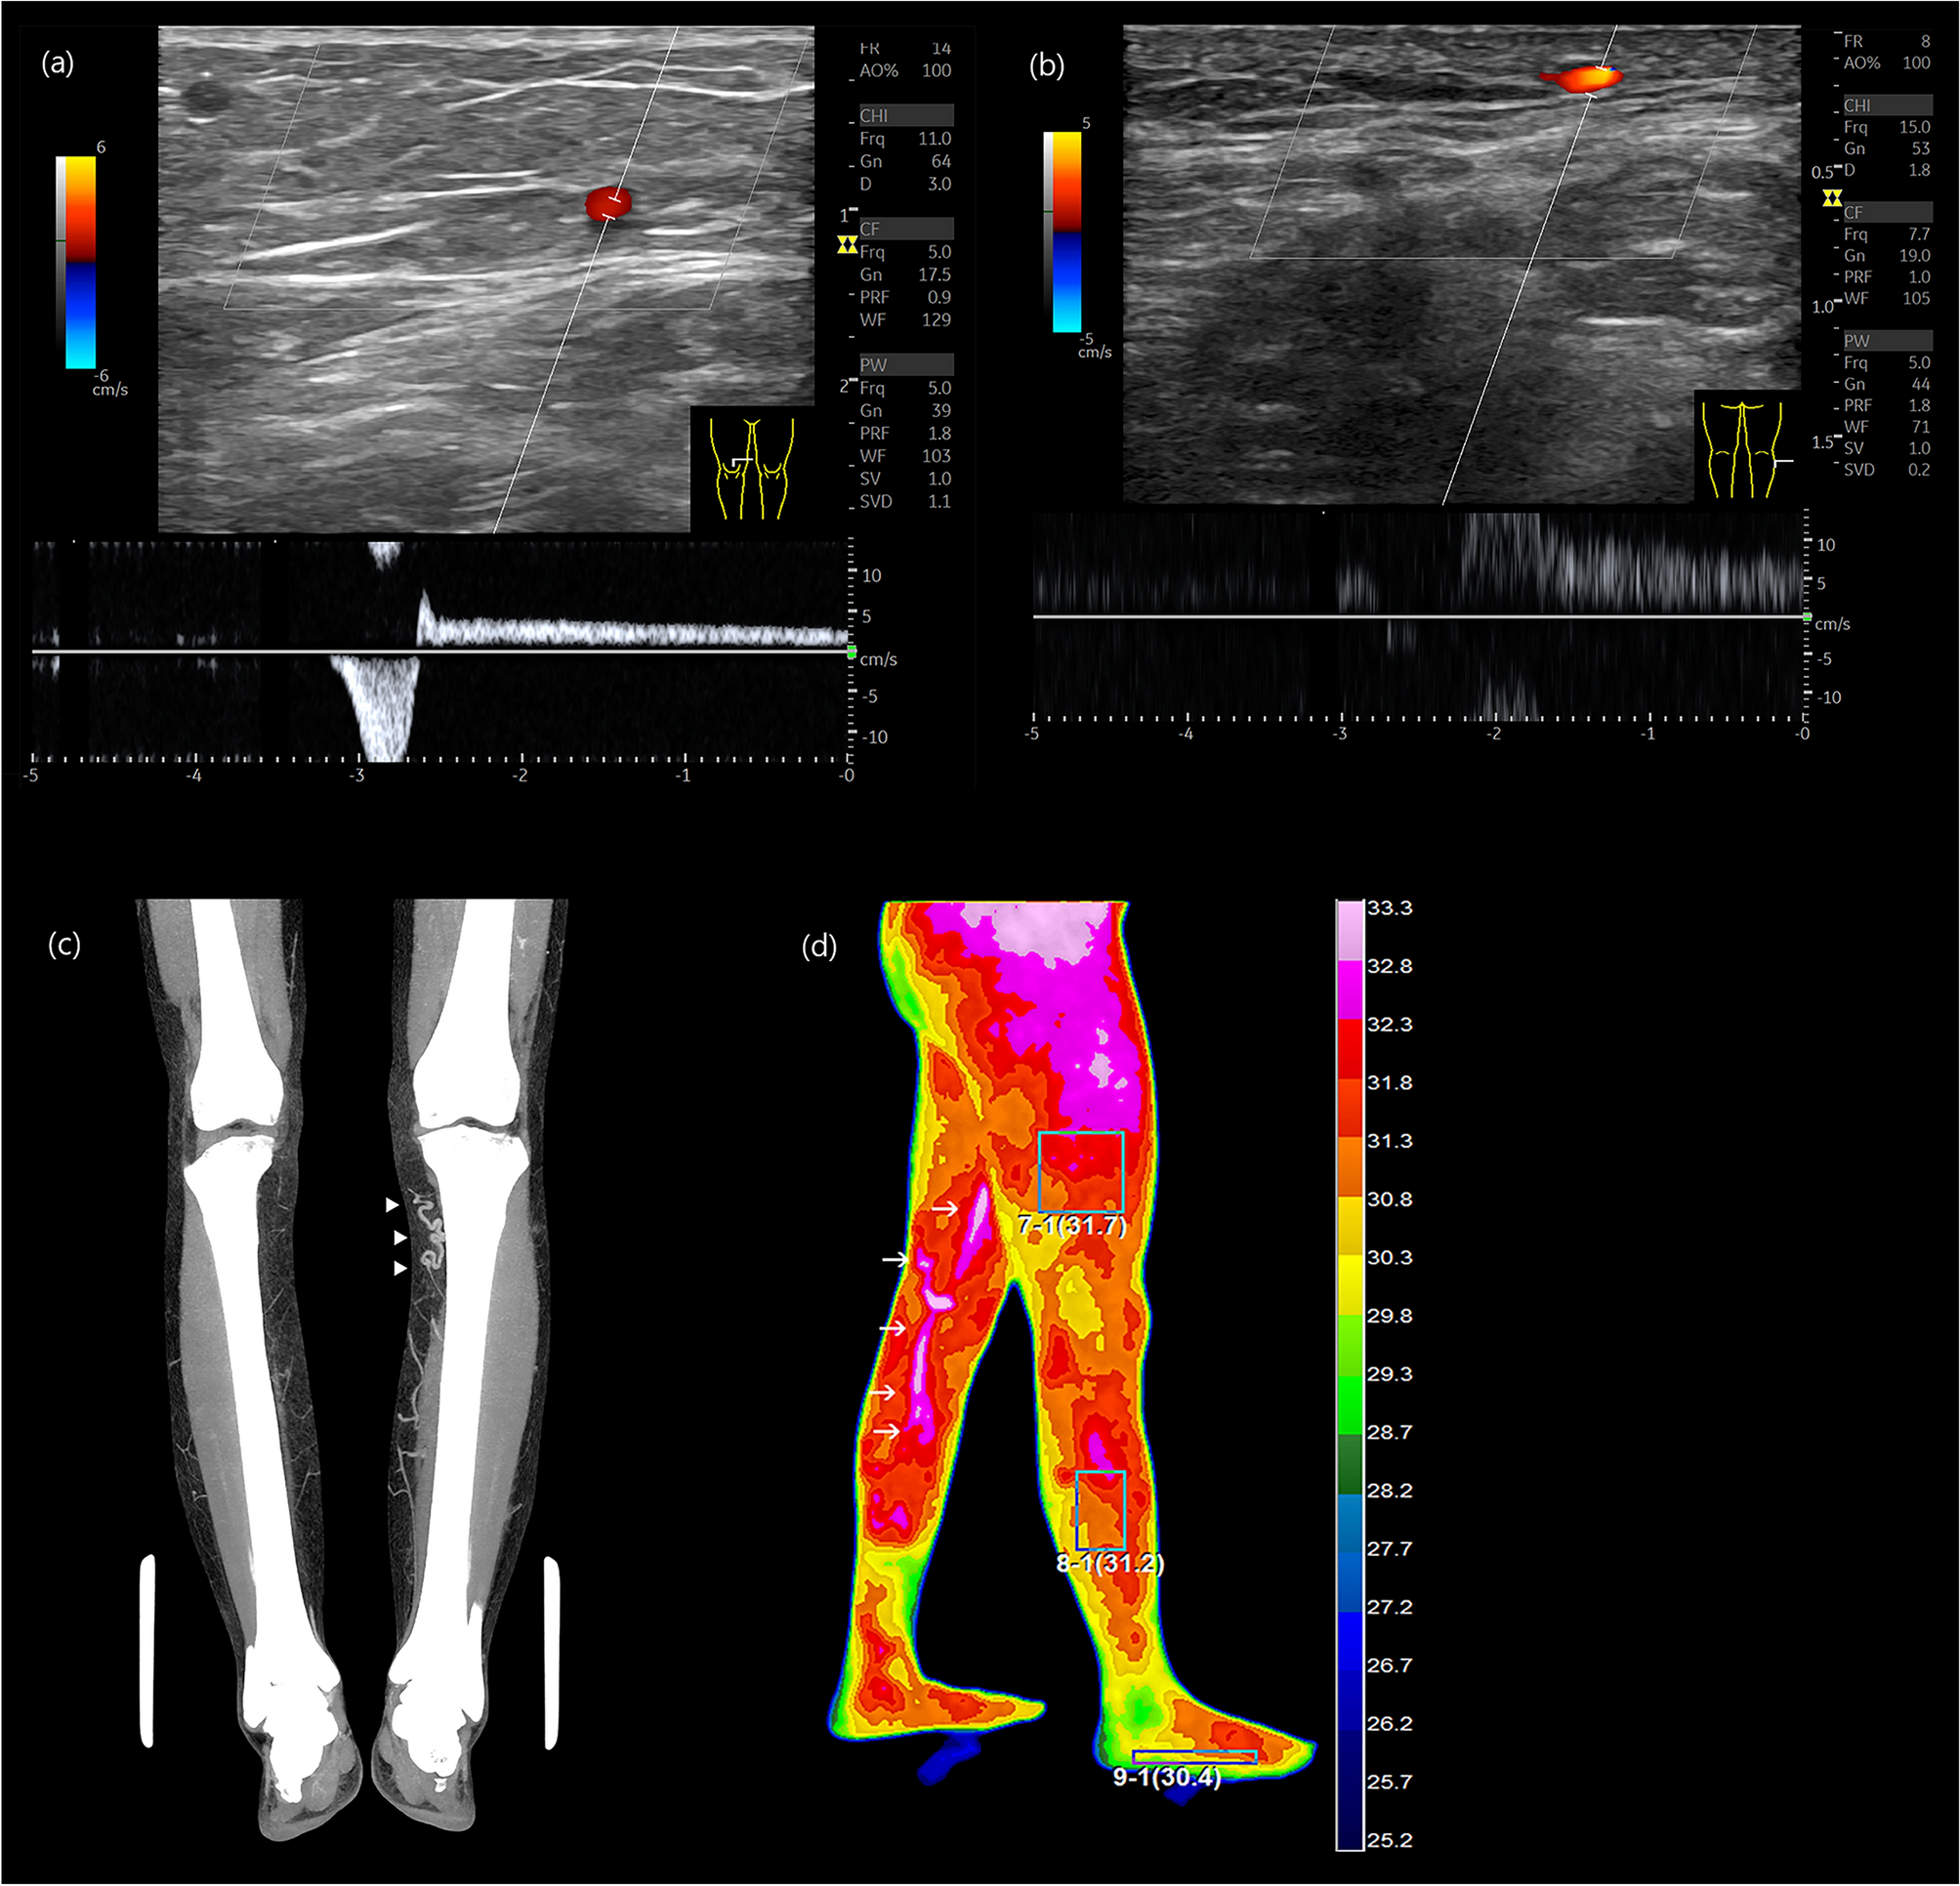

Figure 4

From: Early-stage chronic venous disorder as a cause of leg pain overlooked for lumbar spinal disease

Diagnosis of CVD. (a) Axial ultrasound image showing GSV reflux at right lower thigh, (b) Axial ultrasound image displaying direct tributary reflux at right lateral calf, (c) Venous phase of lower extremity CT revealing a tortuous GSV at left upper calf indicating varicose change (arrowhead), (d) DITI showing GSV reflux at left medial thigh and calf (arrow).